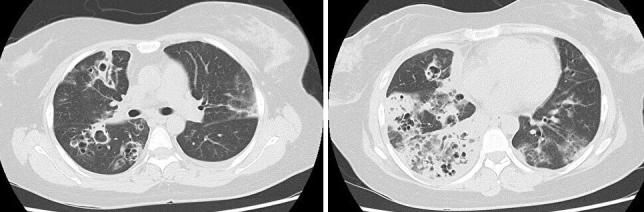

Necrotizing Pneumonia Caused by Community-acquired Methicillin-resistant Staphylococcus aureus Following Influenza.

Abstract Image